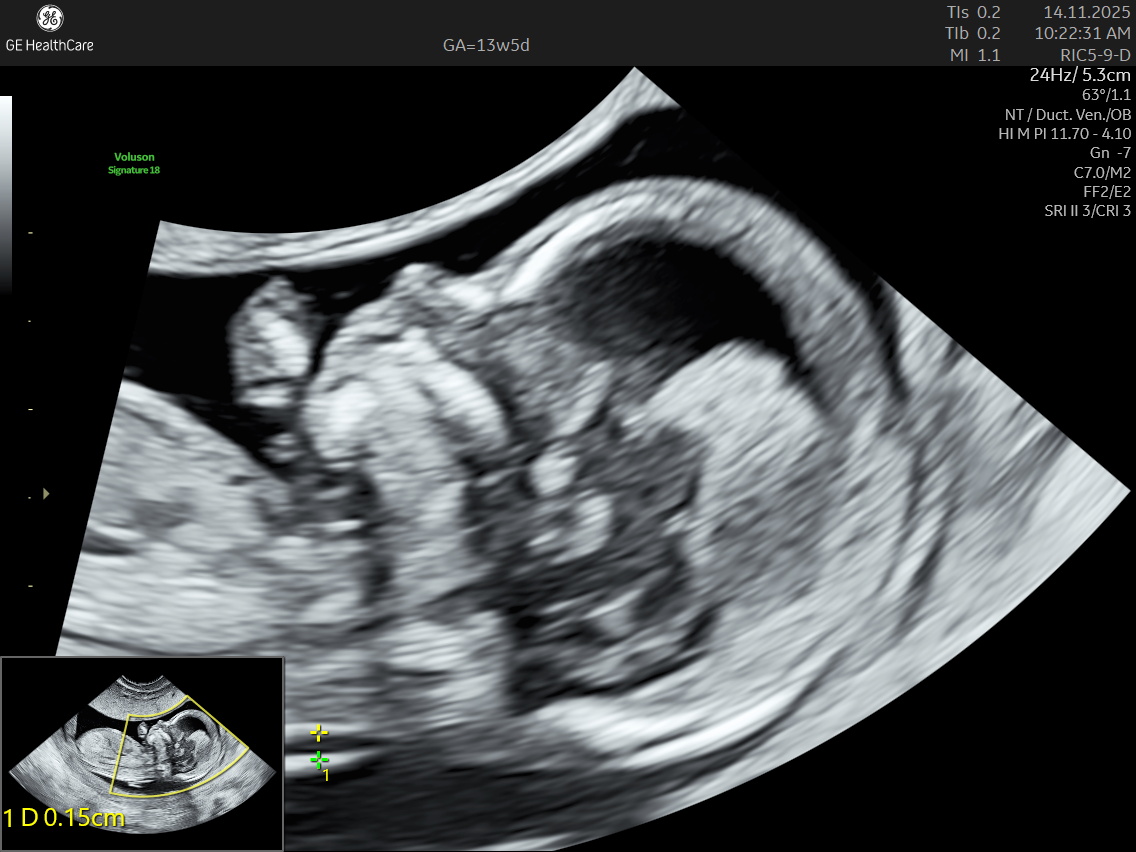

Nuchal Translucency Scan at NESA Institute of Fetal Medicine, Kolkata

NESA Institute of Fetal Medicine offers specialized first-trimester screening for expectant parents, delivering high-precision NT scans between 12 to 13 weeks of pregnancy. Our experienced fetal medicine team ensures accurate risk assessment for chromosomal abnormalities, including Down syndrome, Edwards syndrome, and Patau syndrome.

The NT scan is a non-invasive ultrasound examination conducted in the first trimester (12–13 weeks). It measures the nuchal translucency (the fluid at the back of the fetus’s neck) and combines it with the maternal blood test for a detailed risk profile. NT Scan is an important early screening test for Down syndrome (Trisomy 21), Edwards syndrome (Trisomy 18), and Patau syndrome (Trisomy 13).